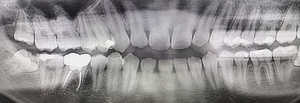

まず、親知らずと骨の中にある神経の位置、歯や周囲の骨の詳細な情報を確認するために、歯科用パノラマデジタル写真で口腔内を撮影します。撮影結果を踏まえ、抜歯方法や施術の難易度をしっかり確認しました。

原因をより詳しく調べるためレントゲンを撮影したところ、右下の親知らずは骨の中に埋まった状態のまま真横に生えて隣接する歯を押しており、前方の歯が虫歯になっています。 そのため、右下の親知らずと隣の奥歯の間には、歯と歯ぐきの境目の溝である「歯周ポケット」が通常よりもかなり深くなっていました。